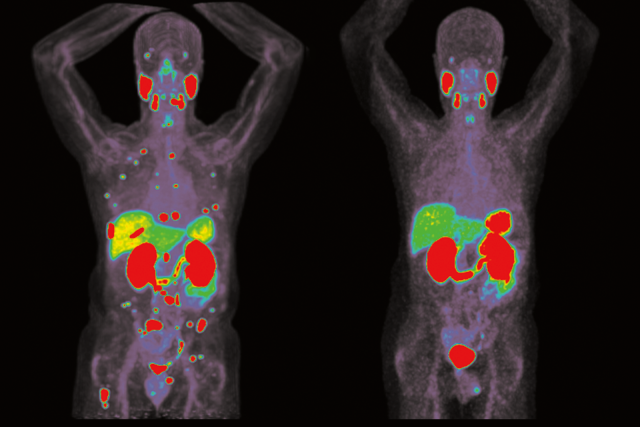

Theranostics cancer treatments scan. Targeted radioactive drugs are used to treat patients with advanced prostate, thyroid and neuroendocrine cancer.

Image: Courtesy of Dr. Jeremie Calais

The term theranostics comes from the words therapeutics and diagnostics. Proteins present on the tumor cells can serve as an anchor for radioactive drugs. Radioactivity can be used to create images with a PET scan that allow doctors to visualize the cancer and then deliver radioactive medicine to kill them.

“It’s the combined use of a therapeutic agent and diagnostic agent that both have the same molecular target,” Dr. Calais said. “You see what you treat and you treat what you see – that’s the concept of theranostics.”

For diagnostics, a patient receives an injection of a tiny amount of a radiotracer that can be detected with a PET scanner to show prostate-specific membrane antigen (PSMA) positive lesions. PSMA is overexpressed in prostate cancer. The injected agent binds to cancer cells so they show up as bright spots on a scan.

“The PET scan tells us exactly whether the therapeutic target is there, and how much of it is expressed in the patient,” Dr. Czernin said. “It’s really a new kind of precision medicine.”